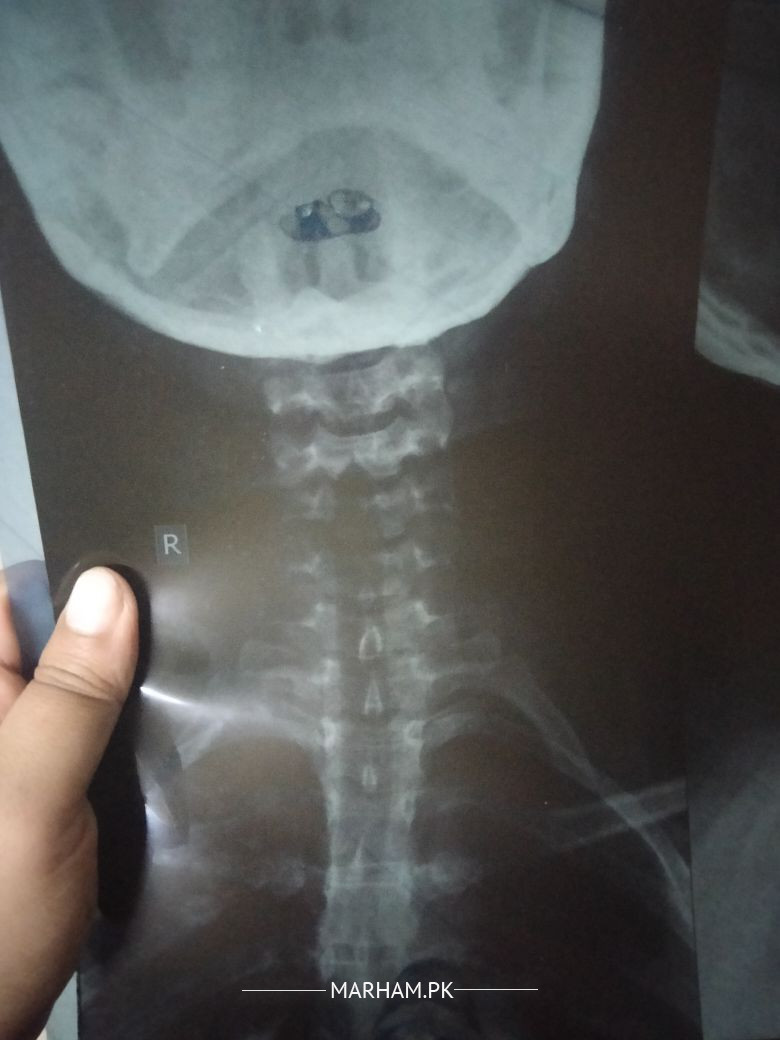

mjhy teen Saal SE neck pain different duwaiya kha chuki hun mjhy six month pehly neck ky neechy sojan feel hui tu doctor ny kaha message ki wja se injury hu gyi hgi duwai di kaha month mn theek hu jae ga ab mjhy wo jaga zyada soji lgty or left side pe bi bht pain hta kamar mn kidney ky saray test theek hn but neck uper SE lekr left tang tak bht khichav mehsos hta plz suggest something duwai bi nhy asar krty derd ky lyr

Attach Photo here: